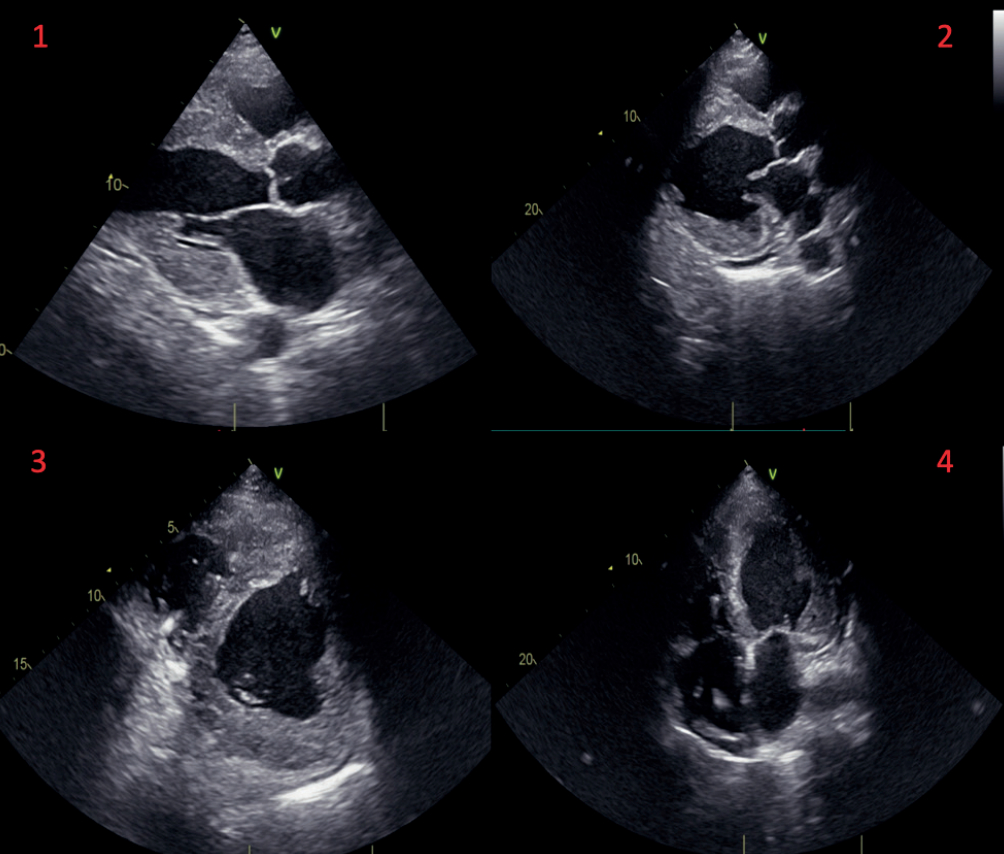

Abstract Body (Do not enter title and authors here): Introduction: Fabry disease (FD), an X-linked lysosomal storage disorder, is caused by mutations in the GLA gene, leading to deficient alpha-galactosidase A activity and subsequent accumulation of glycosphingolipids in various organs. The cardiac manifestations can closely resemble those of hypertrophic cardiomyopathy (HCM), making it a diagnostic challenge, particularly when presenting without the hallmark systemic symptoms of FD, such as pain crises or skin lesions. Case Report: A 64-year-old male with a history of decompensated heart failure was initially diagnosed with HCM after presenting with severe concentric left ventricular hypertrophy and a reduced ejection fraction (25%). Despite undergoing cardiac resynchronization therapy, the patient's condition continued to deteriorate, ultimately leading to the need for heart transplantation. In the post-transplantation phase, a first-degree relative was diagnosed with Fabry disease. This prompted a reconsideration of the diagnosis. Enzymatic analysis of the explanted heart tissue revealed a significant reduction in alpha-galactosidase A activity (0.28 µmol/L/h; reference >1.68), and genetic testing confirmed a pathogenic variant (p.N215S) in the GLA gene. Histopathological examination of the explanted heart demonstrated glycosphingolipid deposition, characteristic of Fabry disease. Discussion: The initial diagnosis of HCM was complicated by the absence of classic systemic symptoms of Fabry disease. Histopathological findings of glycosphingolipid accumulation in the myocardium confirmed the diagnosis, shedding light on the overlap between HCM and Fabry disease. This case illustrates that, while enzyme replacement therapy (ERT) can help manage Fabry disease, the key to improving outcomes lies in early detection. Unfortunately, by the time the diagnosis was made in this case, the patient’s disease had progressed to end-stage heart failure, highlighting the crucial need for awareness and early diagnosis. Conclusion: This case emphasizes the diagnostic importance of considering FD in patients with unexplained hypertrophic cardiomyopathy or progressive heart failure. Family history, along with advanced diagnostic tools like genetic testing and enzymatic analysis, should guide clinicians to reconsider initial diagnoses. Early identification could significantly alter the management course, optimizing the benefits of enzyme replacement therapy and preventing the progression to advanced heart failure.